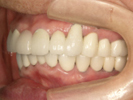

40代女性

奥歯が欠落して、全く噛めないと大変お困りの状態でした。

治療に1年半程要しましたが、熱心に通院してくださいました。

魚介類・お肉なんでも噛めるようになり、今ではニコッと笑える日々で楽しいですと、

アンケートにも答えてくださいました。

![]() |

| 治療前 | ||

| 治療後 | ||